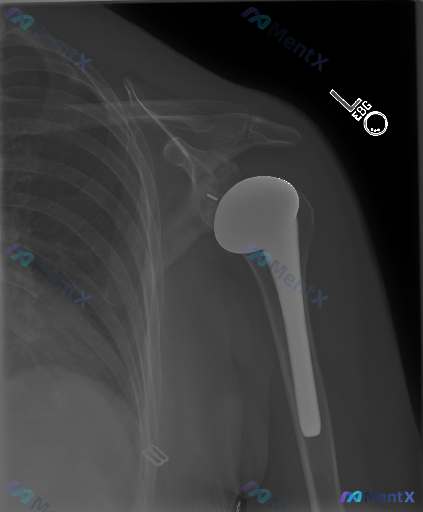

整理到一张左肩正位X光片的阅片资料,大家可以先看一下核心表现:

- 左侧肩关节已行置换术,肱骨头为金属假体,有髓内柄

- 假体位置看起来居中,肩胛盂对位尚可

- 假体周围未见明显透亮线

- 关节盂附近和下胸壁还有点小的金属高密度影

- 没看到明确的急性骨折、脱位或恶性骨破坏